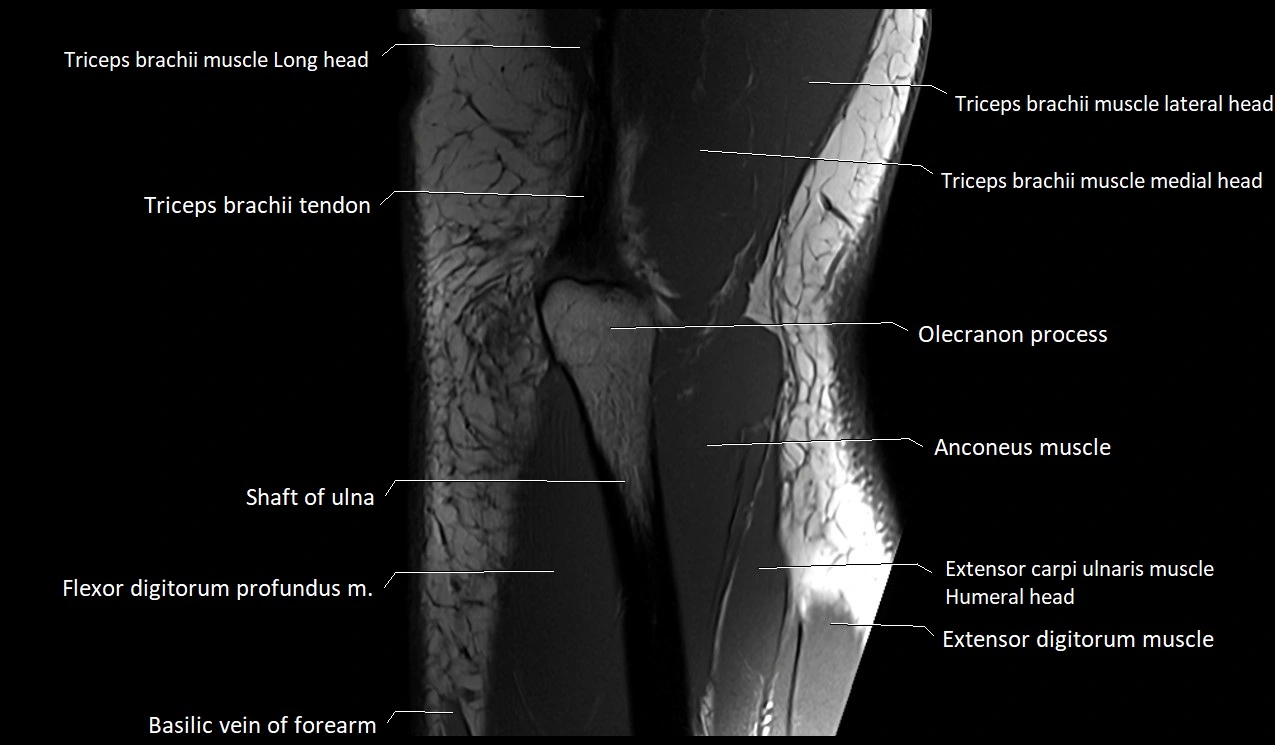

MRI image

image